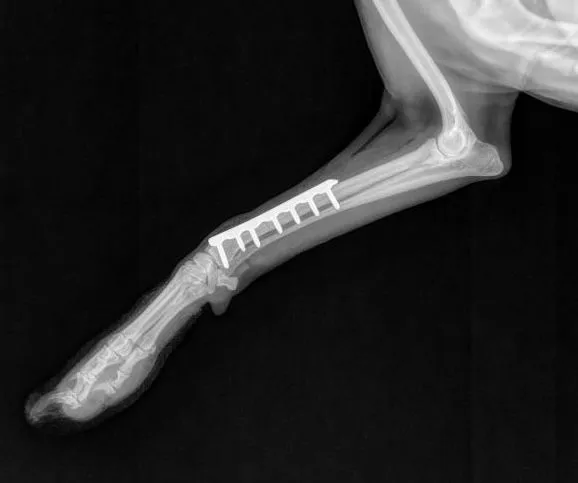

- Fracture repair (Plating, plate/rod, cross pin, compressive screw, etc.)

Fracture Repair Services

At Caring Hands, while our doctors are general surgeons and not board-certified orthopedists/surgeons, they are orthopedically trained by the AO organization which is a prestigious international orthopedic foundation that focuses on orthopedic care in both human and veterinary patients. We offer robust fracture repair options through the use of high-quality plating systems, rods, pins, wires, and screws. If you're worried that your furry loved one has broken his/her leg, our doctors will start by taking x-rays and then will develop a plan using special fracture planning software before operating. We will provide you an honest estimate, and provide you with several options of how to carry that plan out which in limited situations may include referral to specialists if its a case we don't feel comfortable operating on. We do take referrals from other hospitals that don't operate on bones! Give us a call and we will happy to serve you in anyway we can.

Caring Hands is proud to use very high quality human-quality orthopedic plating equipment (Movora/VOI) and orthopedic drills (Stryker)